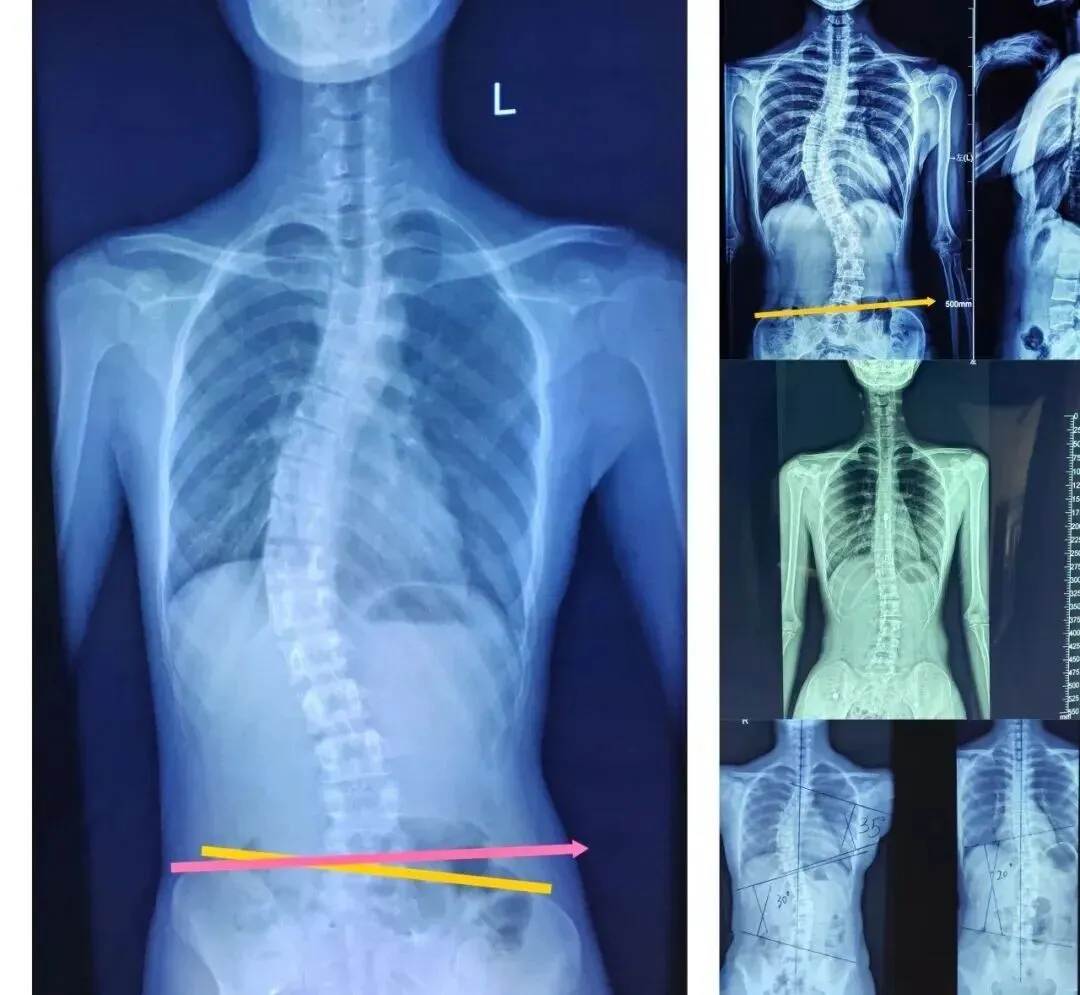

如今,脊柱侧弯已成为继肥胖、近视之后,威胁我国儿童青少年身心健康的第三大“杀手”。它起病隐匿,在6-18岁青少年生长发育关键期进展迅速,初期仅表现为体态异常,很容易被家长忽视。

若未能及时发现和干预,不仅会影响孩子的体态美观,严重时还会压迫心肺功能,限制生长发育,甚至对未来的升学、就业造成深远影响。